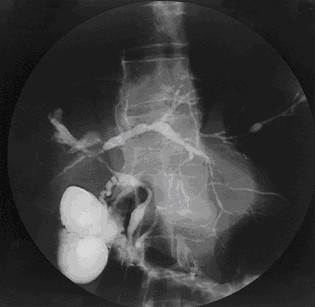

El diagnóstico de colangitis esclerosante primaria (CEP) se ha mejorado con el uso cada vez más frecuente de la colangiografía por resonancia magnética (MRCP, por sus siglas en inglés), cuya…